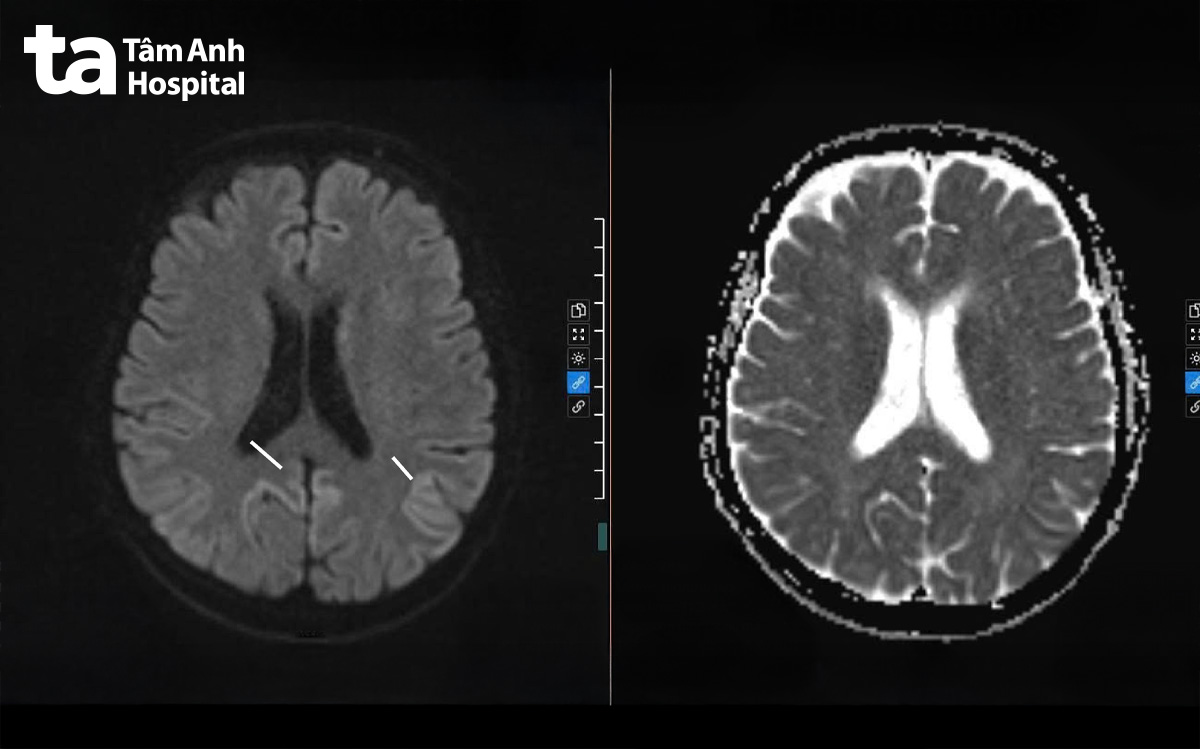

Chụp MRI 3 Tesla cho thấy nhiều vùng bất thường ở vỏ não và một số cấu trúc sâu trong não, hình ảnh gợi ý bệnh Creutzfeldt-Jakob (CJD). Điện não đồ ghi nhận sóng chậm lan tỏa ở cả hai bán cầu, cho thấy não đang bị tổn thương. Ông Tấn được chỉ định xét nghiệm dịch não tủy phát hiện protein 14-3-3 tăng cao (82 ng/mL), là dấu ấn sinh học quan trọng giúp củng cố chẩn đoán bệnh liên quan prion.

Bác sĩ Hạnh Tiên khuyến cáo người lớn tuổi xuất hiện sa sút trí tuệ diễn tiến nhanh trong vài tuần đến vài tháng, kèm rối loạn thăng bằng, thay đổi hành vi hoặc rối loạn thị giác cần được thăm khám chuyên khoa thần kinh sớm. Chụp MRI não với kỹ thuật khuếch tán, điện não đồ và các xét nghiệm dấu ấn sinh học đóng vai trò quan trọng trong chẩn đoán, giúp phân biệt với các nguyên nhân có thể điều trị được như viêm não, bệnh tự miễn hay rối loạn chuyển hóa.